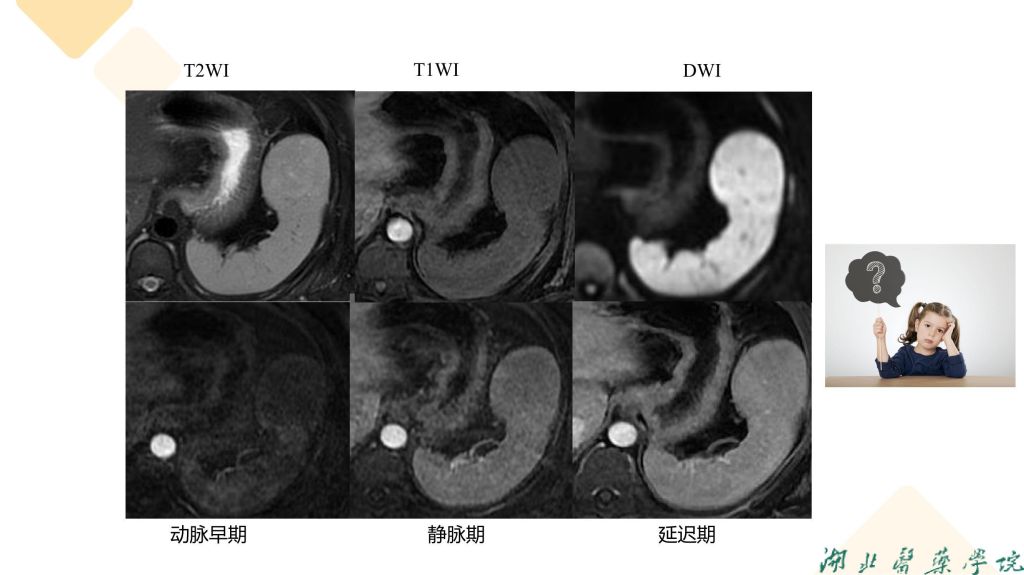

病例分享-脾脏实质性占位性病变